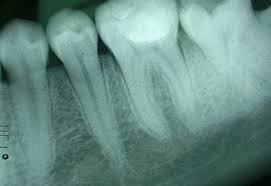

Eine Röntgenaufnahme beim Zahnarzt eine beim Orthopäden und eine wegen einer starken Bronchitis mit Verdacht auf Lungenentzündung - so schnell kann es zu mehreren Röntgenaufnahmen im Jahr kommen. 2012-01-03 171048 2386 1234. Die natürliche Strahlung der Erde entspricht pro Jahr etwa 100 Grossröntgen- oder 400 Zahnfilm-Aufnahmen.

Bei mir müßten die gesamten Zähne mehrmals sehr oft in diesem Jahr geröntgt werden. Wie oft sollte man sich im Jahr nur höchstens beim Zahnarzt röntgen lassen. Bereits 2009 wurden 2 Aufnahmen gemacht.

Wir versuchen die Röntgenaufnahmen dabei auf ein Minimum zu beschränken getreu dem Motto so wenig wie möglich so viel wie nötig. Sie muss zehn Jahre lang aufbewahrt werden. Das Zahnrönt-gen stellt somit ein wenig belastendes Diagnoseverfahren dar das im Verhältnis zur. Hallo ich möchte gern wisenwie oft ein 10 jähriger den Röntgenstrahlen in einem Jahr und allgemein ausgesetzt werden sollte ohnedass es für ihn gefährlich ist. So wenig wie möglich so viel wie nötig. 2x ist sicher besser aber die Entscheidung wie oft man das macht lasse ich mir nicht vom Zahnarzt. Die gesamte Mundsituation Frage vom. Mein Sohn 10 J ist in kieferorth. Ein Bekannter erzählte mir heute dass er bei seinen letzten drei Zahnarztbesuchen die allerdings auch schon vier Jahre auseinander lagen jeweils geröntgt worden sei.

Da ich selbst nächste Woche einen Termin dort habe wollte ich einmal fragen ob ich der einzige bin der. Die jährliche Maximalbelastung sollte pro Person aber nur bei 1 mSv liegen. Bei mir müßten die gesamten Zähne mehrmals sehr oft in diesem Jahr geröntgt werden. Das Zahnrönt-gen stellt somit ein wenig belastendes Diagnoseverfahren dar das im Verhältnis zur. Die Anwendung von Röntgen erfolgt nach dem strengen Grundsatz. Röntgen während der Schwangerschaft. Mit einer Schädigung des Ungeborenen ist theoretisch erst ab 30 mSV zu rechnen das bedeutet dass man den Zahn einer Schwangeren mehr als 500 mal röntgen müsste bis der Fetus geschädigt werden könnte.